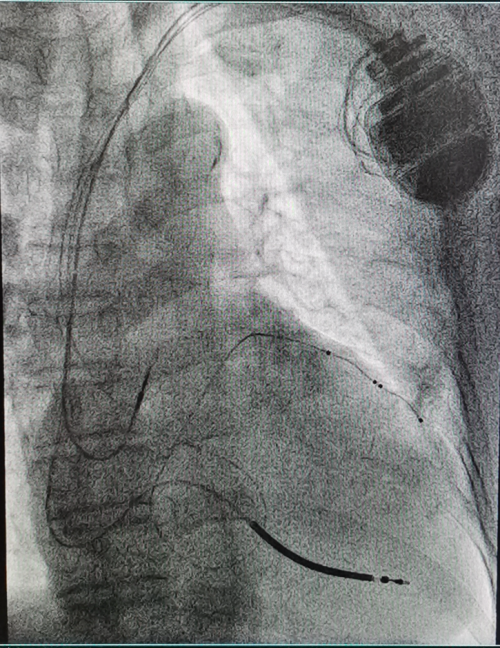

CRT-D重启“心”生,重获“心”力 ——衡阳市第一人民医院成功开展衡阳地区首例3.0T MRI兼容CRTD植入术

(通讯员 彭彦 邹勇)近日,衡阳市第一人民医院心血管内科专家团队成功为一名终末期心力衰竭患者,实施了衡阳地区首例3.0T磁共振(MRI)兼容心脏再同步化治疗心律转复除颤器(CRT-D)植入术。此项技术的开展,填补了区域内该领域的技术空白,标志着该院心脏起搏与电生理诊疗技术实现了跨越式提升,为当地心衰患者带来了新的生命守护方案。

作为心力衰竭治疗的“终极武器”之一,CRT-D(俗称“三腔除颤器”)是集治疗与防护于一体的高端医疗设备。它既具备心脏再同步治疗(CRT)的核心作用,又拥有植入式心律转复除颤器(ICD)的急救功能,为患者的生命安全拴上“双保险”。此次手术的关键突破在于“3.0T MRI兼容”。传统CRTD设备因受电磁兼容性限制,患者术后无法接受高磁场强MRI检查,而MRI作为多种疾病(如肿瘤、脑血管疾病)的重要诊查手段,其检查限制往往给患者后续诊疗带来极大困扰。3.0T MRI兼容型CRTD的成功应用,彻底打破了这一壁垒,患者术后可自由接受3.0T MRI检查,既不影响设备正常工作,又能获得全面精准的后续诊断,极大提升了治疗的安全性与便利性。